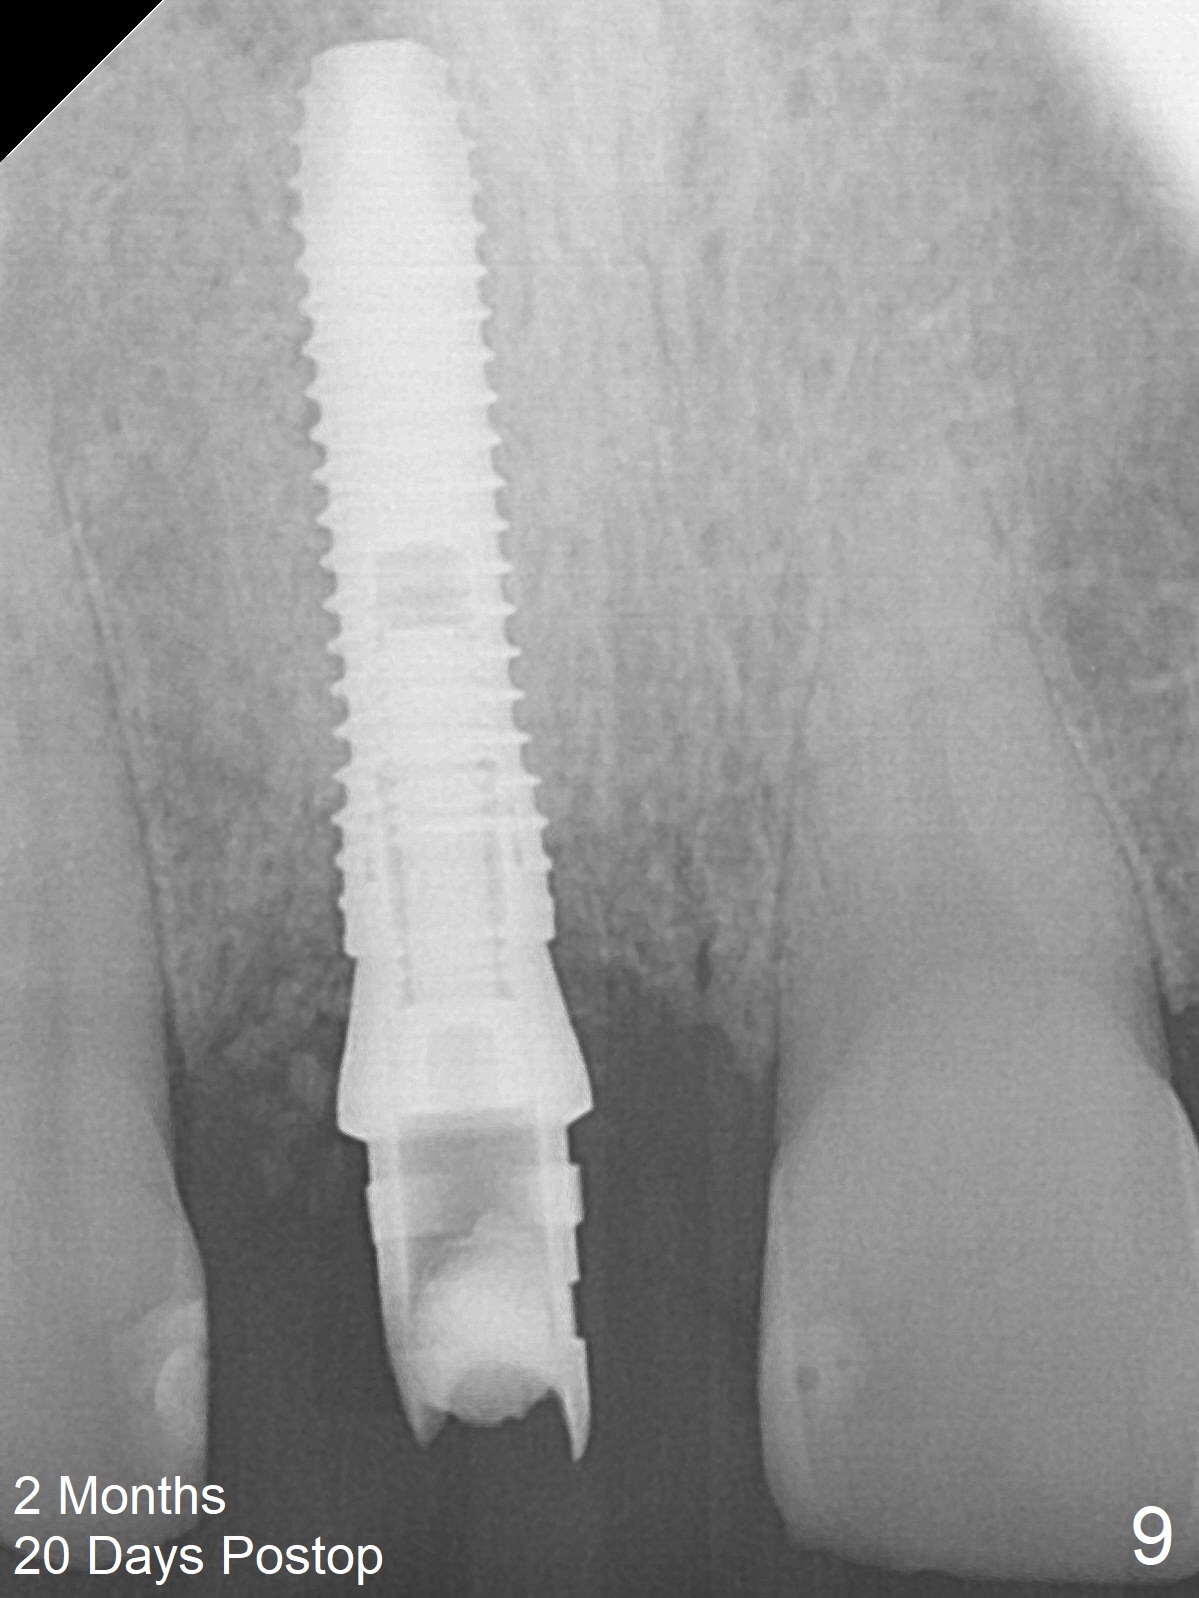

The buccal gingiva at #8 is erythematous (Fig.1: *), which is associated with the tooth fracture line (Fig.2 with granulation tissue: *). The buccal plate remains intact. Osteotomy is initiated in the palatal wall of the socket (Fig.3,4). The initial osteotomy depth is 16 mm (Fig.5); the trajectory is going to be adjusted as shown by arrows. The trajectory improves when a 3.8x15 mm dummy implant is placed (Fig.6). The definitive implant (3.8x16 mm) appears to be placed at an appropriate level (Fig.7). A 4.5x3 mm temporary abutment is inserted for an immediate provisional. As routine, Vera Graft is placed in the buccal gap. The buccal gingival erythema reduces without tenderness 1 week postop (Fig.8). Although the provisional is unstable, there is no bone loss 2 months 20 days postop (Fig.9). Because of the loose provisional (partial detachment from the underlying temporary abutment), impression is taken earlier (3 months postop, Fig.10,11). Due to the pointed abutment tip, the crown is redone 3 times. By the time of cementation (nearly 5 months postop), the socket appears to have healed (Fig.12).